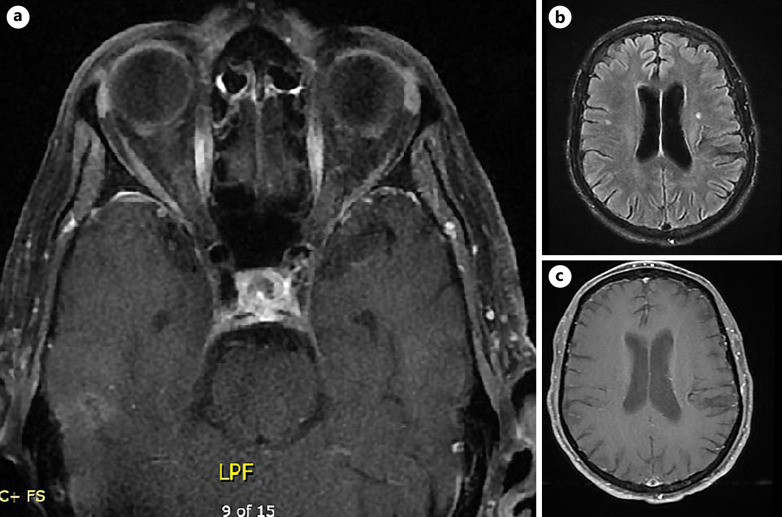

Case presentation: We describe a case of a 64-year-old woman who presented with a clinical picture that was suggestive of anterior arteritic ischemic optic neuropathy due to giant cell arteritis (GCA), but was found to have calciphylaxis confirmed by histologic examination. When calciphylaxis affects the blood supply to the eye, commonly it causes sudden vision loss, pallid optic disk edema, and a relative afferent pupillary defect, all of which were observed in our patient.